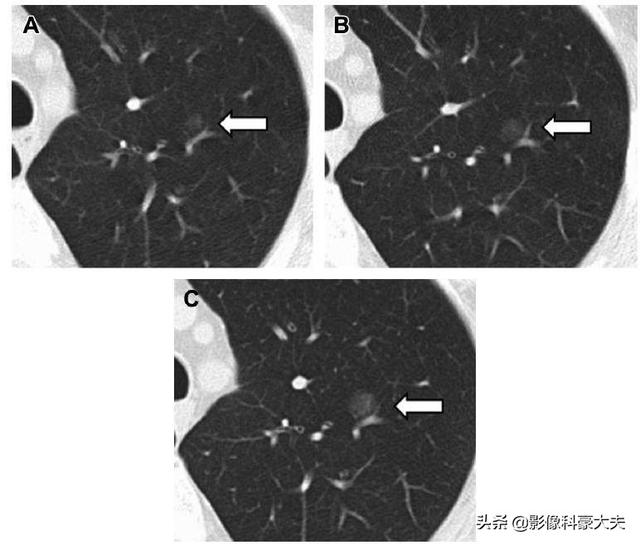

Eine Bösartigkeit wird meist in Betracht gezogen, wenn folgende Veränderungen auftreten: eine allmähliche Zunahme des Knötchendurchmessers mit einer kurzen Verdopplungszeit; das Vorhandensein einer festen Komponente in der knotigen Läsion; oder das Vorhandensein einer festen Komponente oder eine Zunahme der festen Komponente in der knotigen Läsion, obwohl die knotige Läsion schrumpft.

Es wird allgemein angenommen, dass, wenn die Größe des Lungenknotens nach 3 Monaten, 6 Monaten oder sogar 1 Jahr der Nachuntersuchung seit der Entdeckung des Lungenknotens durch CT unverändert ist oder sogar schrumpft, dies auf eine höhere Wahrscheinlichkeit gutartiger Lungenknoten hinweist.

Wenn sich die Lungenknötchen innerhalb von 3 oder 6 Monaten nach dem CT-Befund vergrößern oder an Größe zunehmen, besteht eine höhere Wahrscheinlichkeit, dass es sich um bösartige Lungenknötchen handelt.